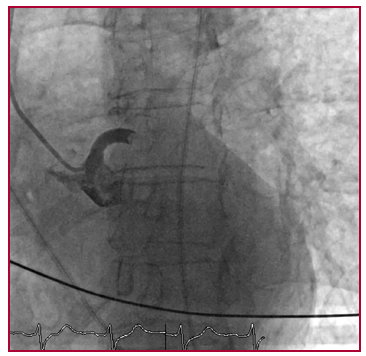

- Diego Vázquez Aller, Uxue Idiazabal Rodríguez, Nora García Ibarrondo, Infarto de músculo papilar posteromedial, diagnóstico por imagen , Revista Argentina de Cardiología: Rev Argent Cardiol 2025 Vol. 93 Nro. 5